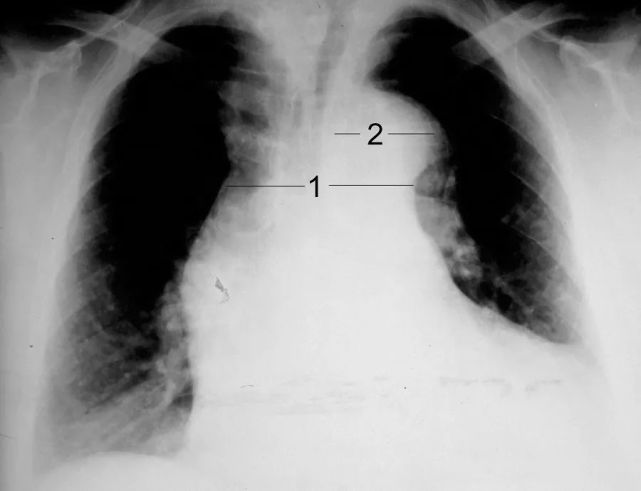

胸腔积液胸片表现图片,胸腔积液胸片典型图片

左侧胸膜肥厚 b . 左侧胸腔积液 c . 左侧液气胸 d . 左侧肺不张 e .

左侧少量胸腔积液.

主动脉夹层患者的胸部x线片(纵膈增宽,左侧胸腔积液)

生活 日常 执业医影像诊断--胸片 {②有阴影:胸腔积液(外高内低)